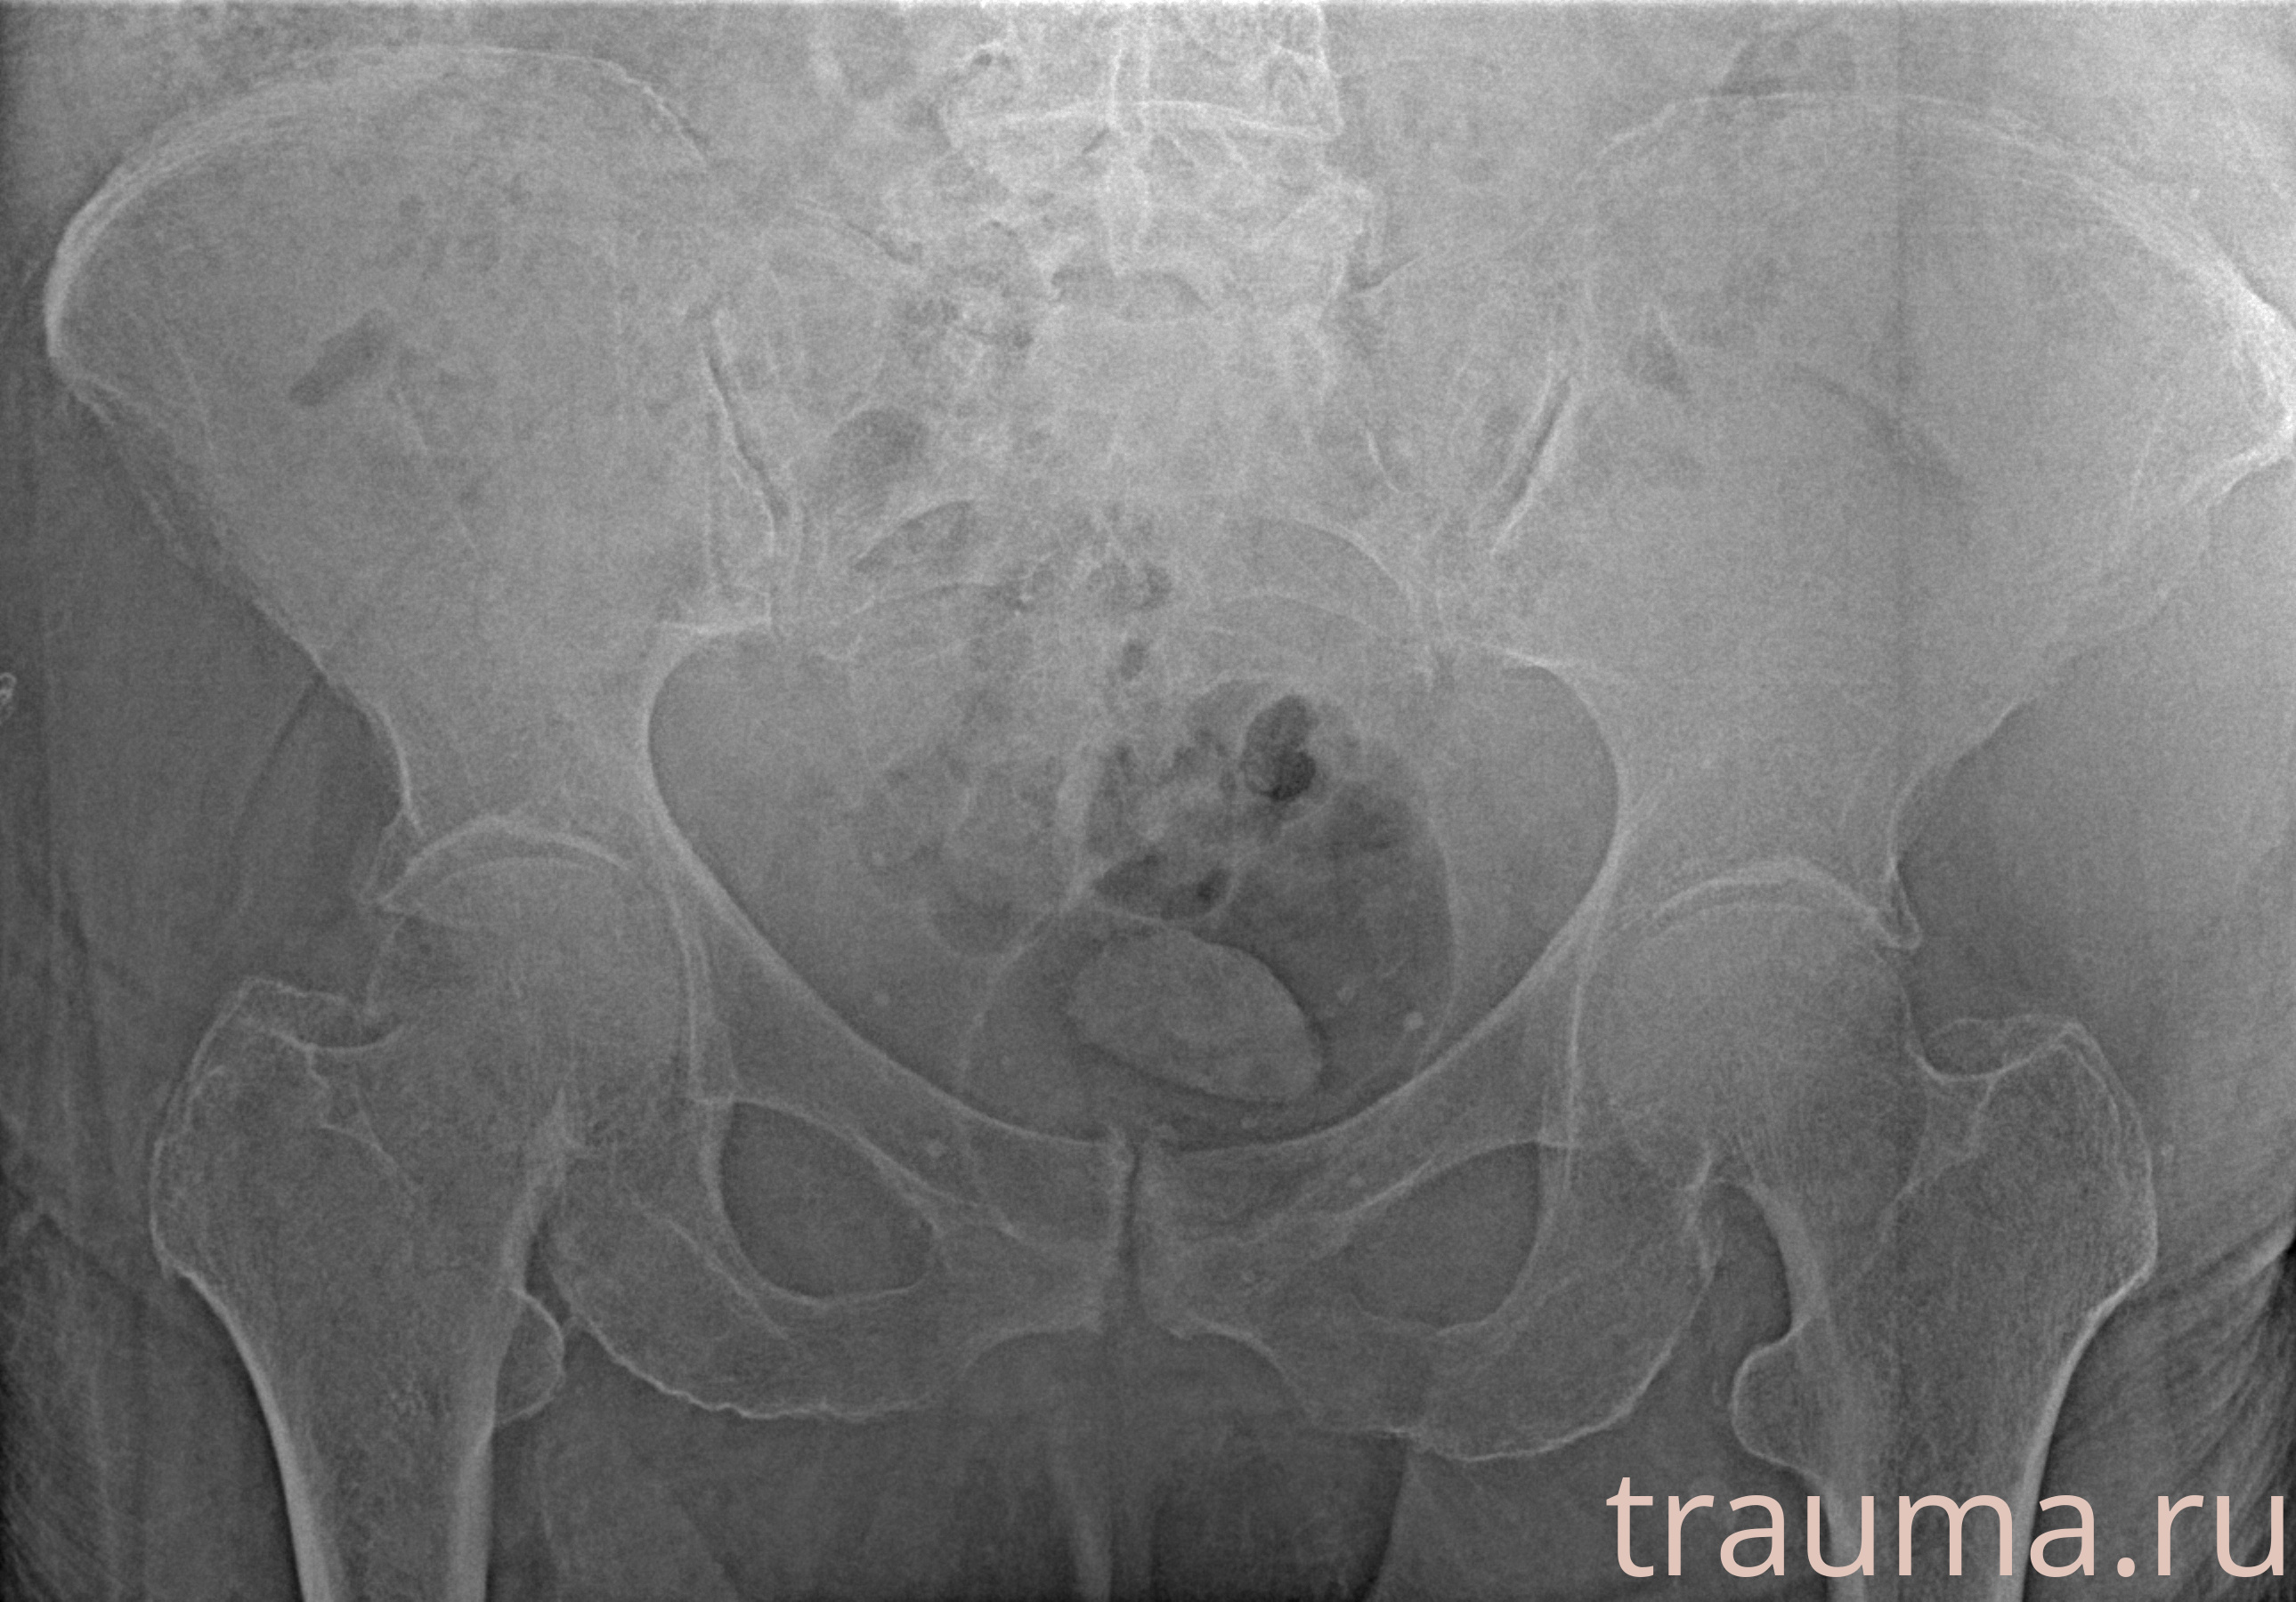

Рентгенограммы

Рентген на дому: по вашему адресу приезжает врач-рентгенолог, травматолог-ортопед с мобильным рентгеновским аппаратом, проводит диагностику травмы или заболевания, делает необходимые рентгенограммы, дает рекомендации по дальнейшему лечению. Получить качественные снимки в домашних условиях возможно благодаря уникальной методике, разработанной МосРентген Центром для института  Склифосовского